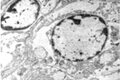

2. Transmission Electron Microscopy Processing unit

Electron Microscopy (EM): Basically two types:

1. Transmission Electron Microscope2. Scanning Electron Microscope

1. Transmission Electron Microscope (TEM) processing unit2. Scanning Electron Microscope (SEM) processing unit3. Ultra Microtome and Histopathology4. Experience in the field of specimen preparation for past 16 years